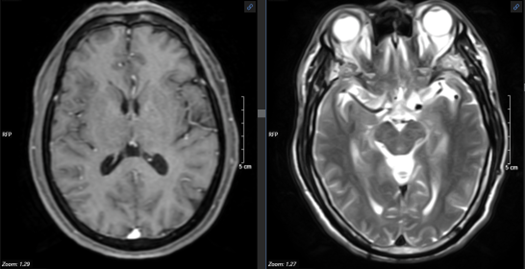

- Chụp cộng hưởng từ sọ não:

Hình 3. Hình ảnh cộng hưởng từ sọ não không thấy tổn thương nghi ngờ thứ phát.